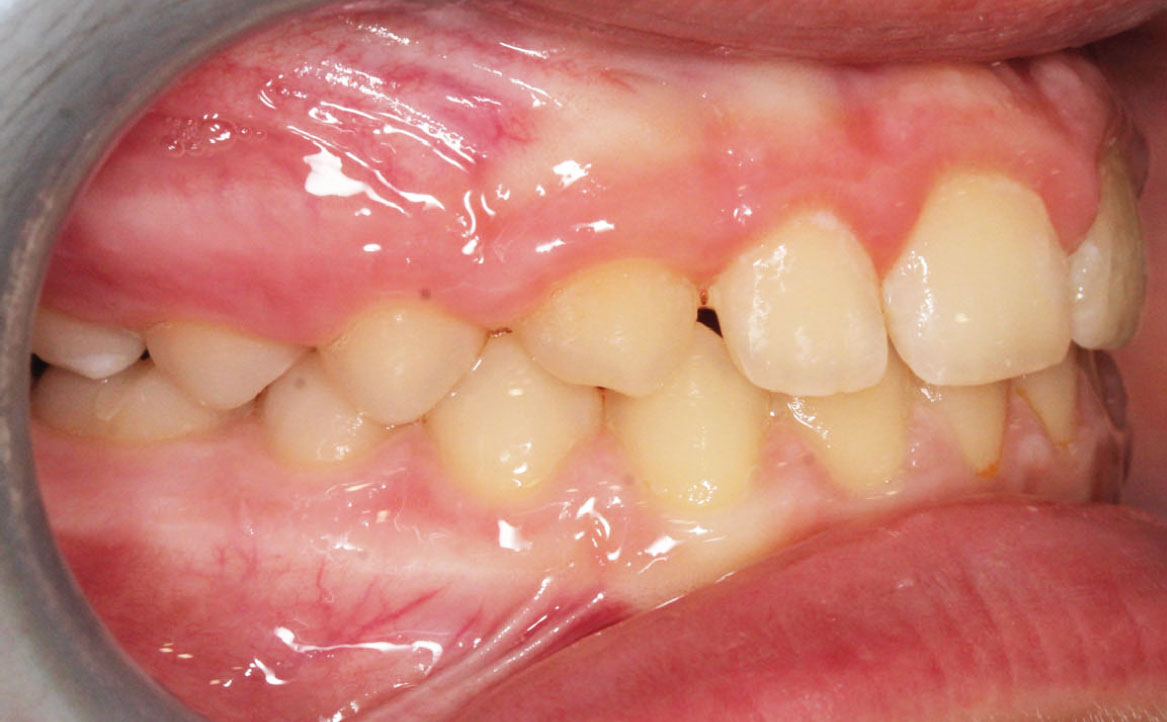

Fig. 4B Foto intraorale in massima intercuspidazione.

A livello intraorale sul piano sagittale è osservabile I classe molare destra e sinistra e classe canina non valutabile per mancanza degli elementi dentari durante la fase di permuta.

L’overjet e l’overbite sono entrambi ridotti in massima intercuspidazione. Trasversalmente il mascellare superiore è contratto (fig. 4-7).